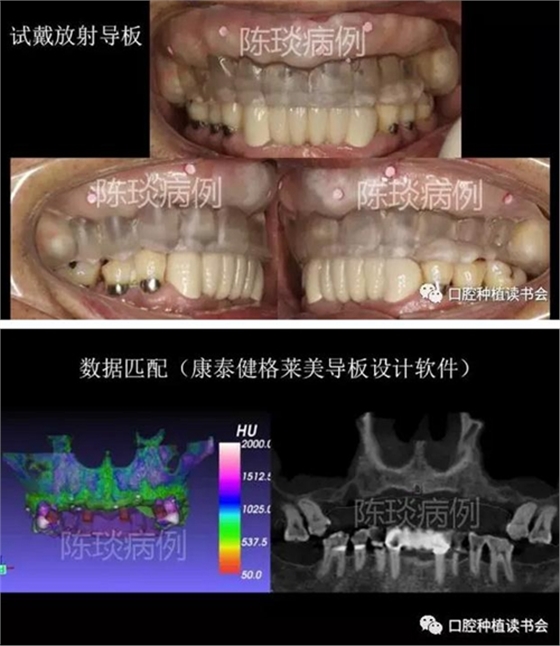

4,數(shù)字化種植導(dǎo)板制作過程:

(1)制作臨時(shí)義齒以及放射導(dǎo)板,根據(jù)石膏模型設(shè)計(jì)放射導(dǎo)板,并確定顯影標(biāo)記。

(2)佩戴放射導(dǎo)板拍CBCT后,設(shè)計(jì)數(shù)字種植導(dǎo)板。